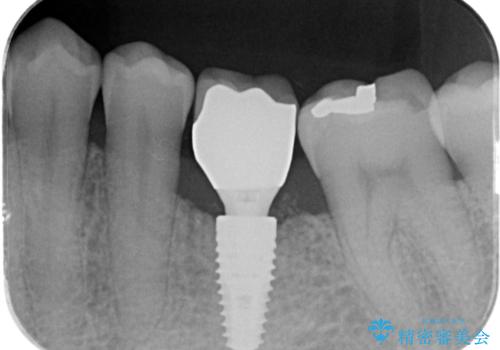

奥歯の欠損 インプラント治療

- 44万円(インプラント・チタンカスタムアバットメント・ジルコニアクラウン・仮歯)費用は治療当時の料金となります

自然な仕上がりと、久しぶりのしっかりと噛める感覚に大変満足いただくことができました。